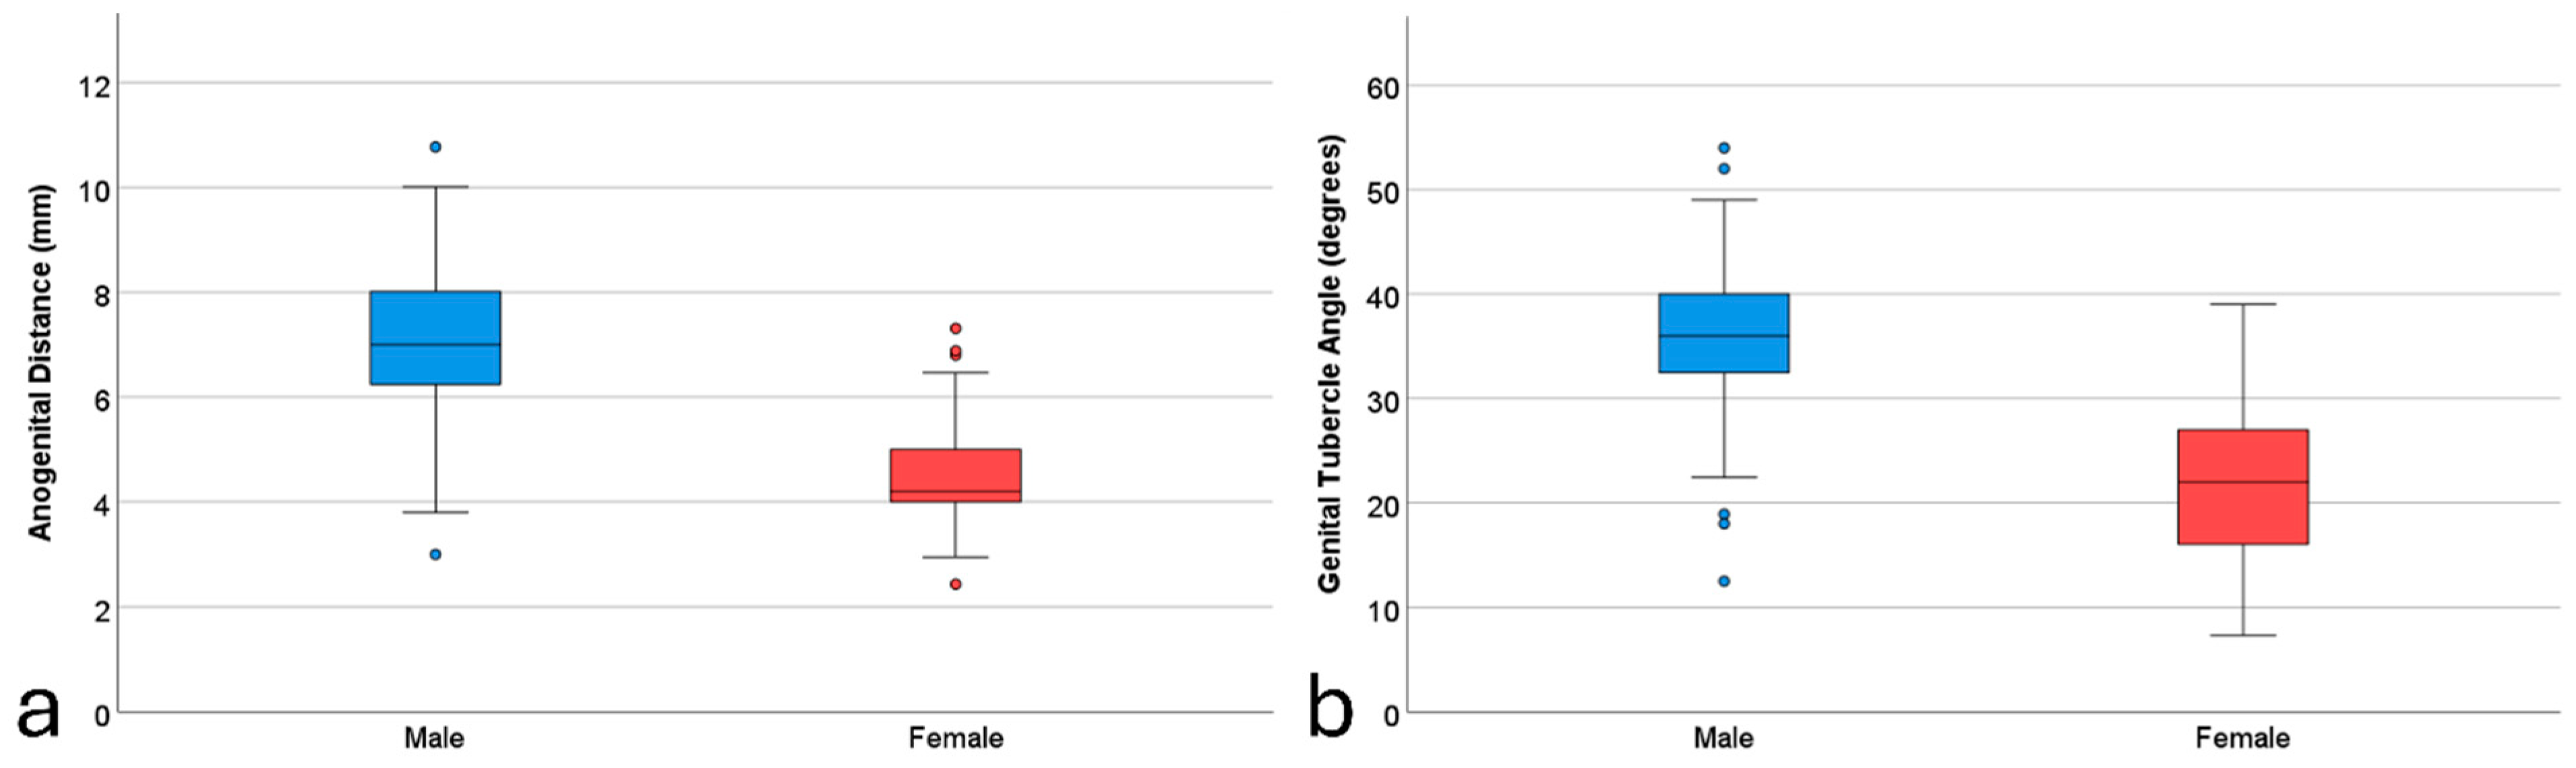

3.1. Descriptive Statistics

| Variable | Male (n = 188) | Female (n = 124) | Overall (n = 312) | |||

|---|---|---|---|---|---|---|

| Mean (SD) | Min–Max | Mean (SD) | Min–Max | Mean (SD) | Min–Max | |

| GA (days) | 87.87 (5.62) | 77–97 | 86.24 (5.78) | 77–97 | 87.22 (5.73) | 77–97 |

| Maternal age (years) | 30.40 (5.19) | 16–44 | 30.17 (4.79) | 19–43 | 30.31 (5.03) | 16–44 |

| CRL (mm) | 61.25 (10.65) | 38.0–85.0 | 58.59 (10.50) | 45.0–83.9 | 60.19 (10.65) | 38.0–85.0 |

| AGD (mm) | 7.16 (1.40) | 3.0–10.77 | 4.42 (1.05) | 2.43–9.0 | 6.07 (1.85) | 2.43–10.77 |

| GTA (degree) | 35.90 (6.20) | 8.13–54.0 | 21.57 (7.29) | 7.32–39.0 | 30.21 (9.67) | 7.32–54.0 |